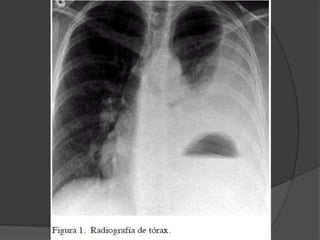

Abombamiento del hemitoráx afectado, con

desviación del esternón hacia el lado opuesto

y disminución de la movilidad respiratoria, se

Existe matidez del hemitoráx comprometido,

si el derrame esta libre la matidez puede

desplazarse con la postura (signo de

desnivel). La columna es mate también.